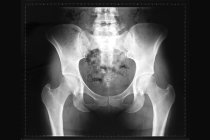

A pelve14 às vezes é envolvida e raramente as costelas5, o esterno15 (osso do peito16) e/ou o crânio4 podem ser afetados. Deformidades também podem se desenvolver nos pulsos e tornozelos. O encurtamento dos membros e o arqueamento dos ossos longos13 podem ocorrer em alguns indivíduos afetados.

O diagnóstico17 da doença de Ollier exige uma completa e detalhada história médica do paciente e inclui biópsia18 óssea, radiografias, ressonância magnética19 e tomografia computadorizada20. As pessoas afetadas devem ser acompanhadas rotineiramente por um médico, como vigilância para alterações malignas nos ossos e articulações21.